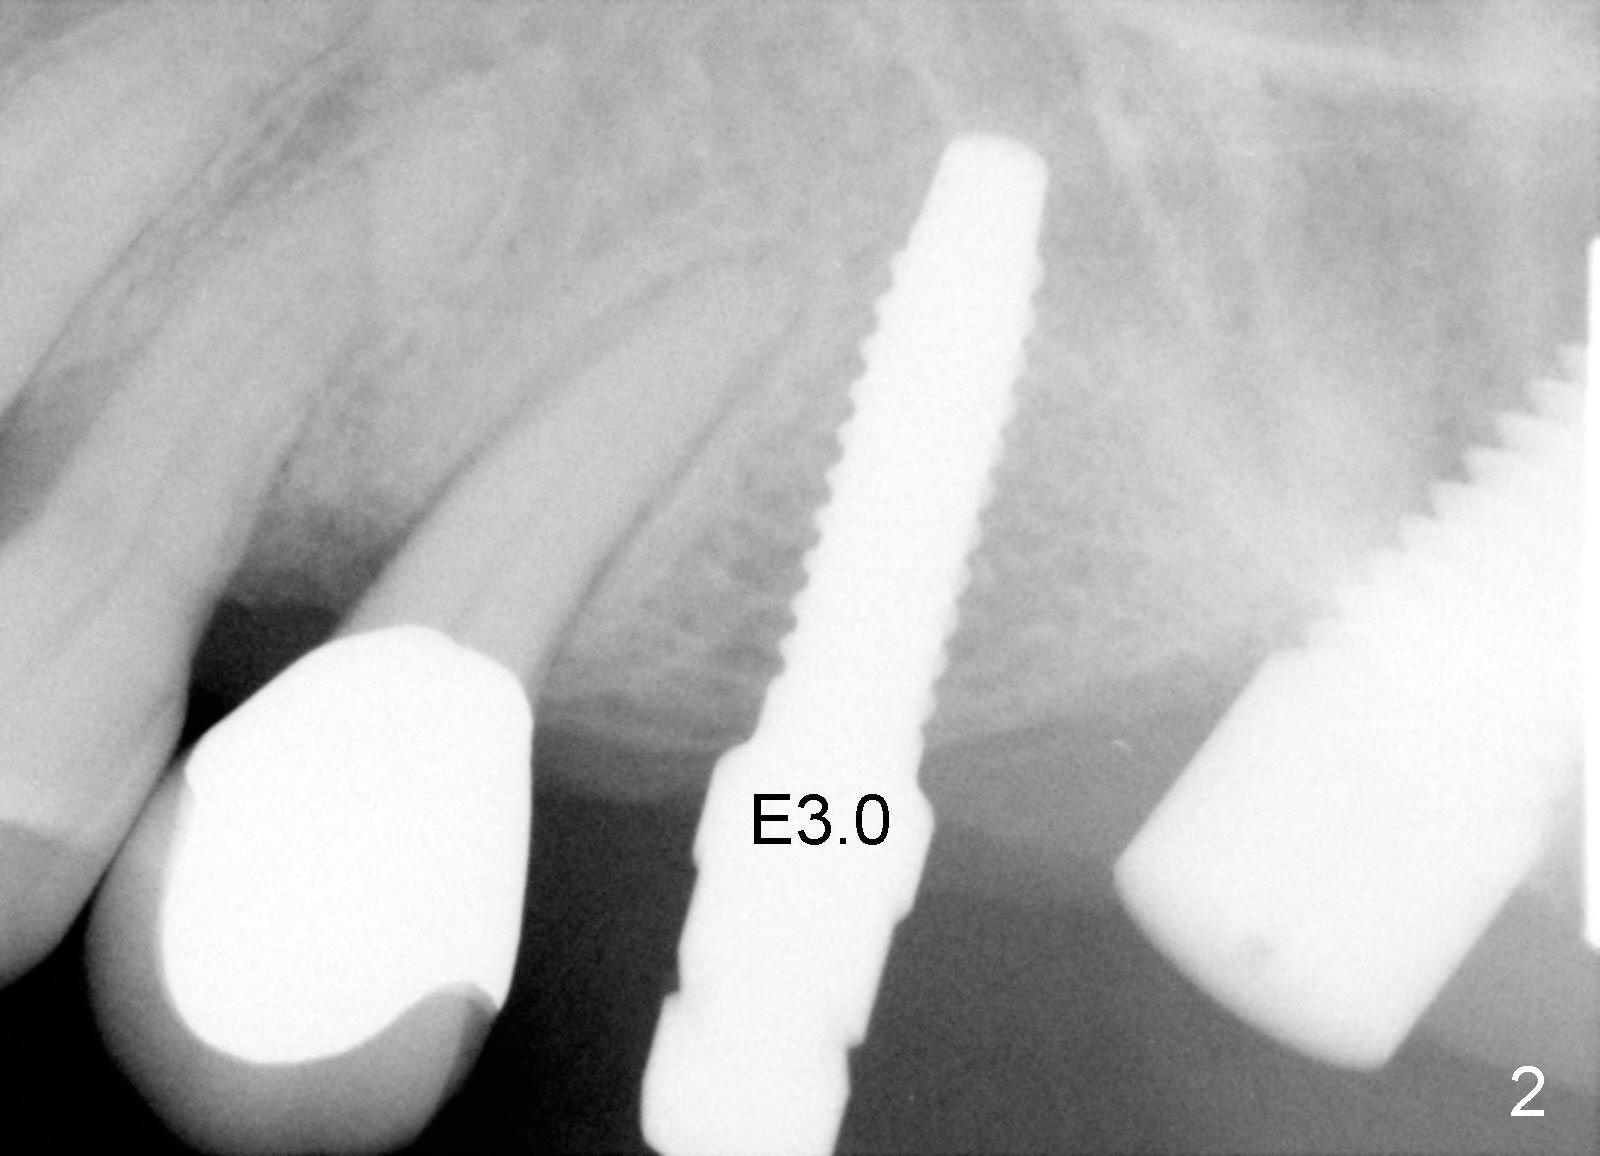

A 58-year-old man used to have a upper left 3-unit bridge. Two months after extraction and immediate implant at the site of the posterior abutment, an implant is planned to be placed at the site of the pontic, #14 (Fig.1). Osteotomy starts with a 1.6 mm pilot drill, followed by bone expanders, parallel to the crown of the tooth #13. The first intraop PA shows that 3.0 mm bone expander is close to the root of the neighboring tooth (Fig.2). No matter what is done to change the trajectory of the osteotomy using expanders according to the crown morphology of the neighboring tooth, the next 3 expander does not improve in parallelism (Fig.3). When a 6x17 mm tap is inserted (Fig.4 T), it is realized that axis of the tap is parallel to the axis of the crown of the neighboring tooth (black line), but not that of the root (red line). It is too late to change the trajectory drastically; a 6x17 mm implant is placed with insertion torque > 60 Ncm (Fig.5). It is best to change the trajectory as early as possible, e.g., after taking the first intraop PA and withdrawing the expander (Fig.6 black area) and as much as possible (red line; starting new osteotomy). It is quite similar to immediate implant. There is no bone loss 2 months postop (Fig.7), 18 months (Fig.8,9) or 34 months (Fig.10)post cementation, in spite of open contact between the crowns (Fig.10 black arrowhead). This is partially due to supragingival margin (Fig.11,12 (immediately pre-cementation)). No bone loss is noted 3 years 5 months post cementation (Fig.13).